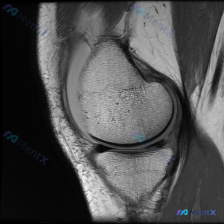

本次仅提供放射影像-膝盖MRI-T1序列-矢状位单张图像,核心问题是询问图像中是否存在半月板异常。

我仔细读了这张片子,所有结构的情况如下:

- 骨骼结构:股骨远端、胫骨近端、髌骨的骨皮质连续,骨髓信号正常,没有看到骨折线、骨质破坏或者局灶性骨挫伤信号,骨皮质边缘光整

- 关节软骨:股骨髁和胫骨平台软骨厚度正常,表面光滑,没有明显变薄、缺损或者软骨下骨暴露,关节间隙没有狭窄

- 半月板(核心问题):这个切面的半月板是均匀低信号,形态完整,没有看到延伸到关节面的异常高信号,前后角形态自然,没有移位或者变形

- 韧带与其他结构:后交叉韧带走行连续信号正常,前交叉韧带近端走行正常;髌下脂肪垫信号均匀,没有看到明确关节积液

读片初步结论:单张T1矢状位影像中,膝关节所有结构都没有看到明确的结构性病理改变,目前属于正常表现。